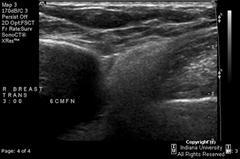

Extracapsular silicone implant rupture

A

Silicone can be seen in breast tissue or lymph nodes after extracapsular rupture.

Classic ultrasound finding of extracapsular rupture is

• “snowstorm” appearance of echogenic scatter in the tissue adjacent to implant.

• “dirty shadow” posteriorly